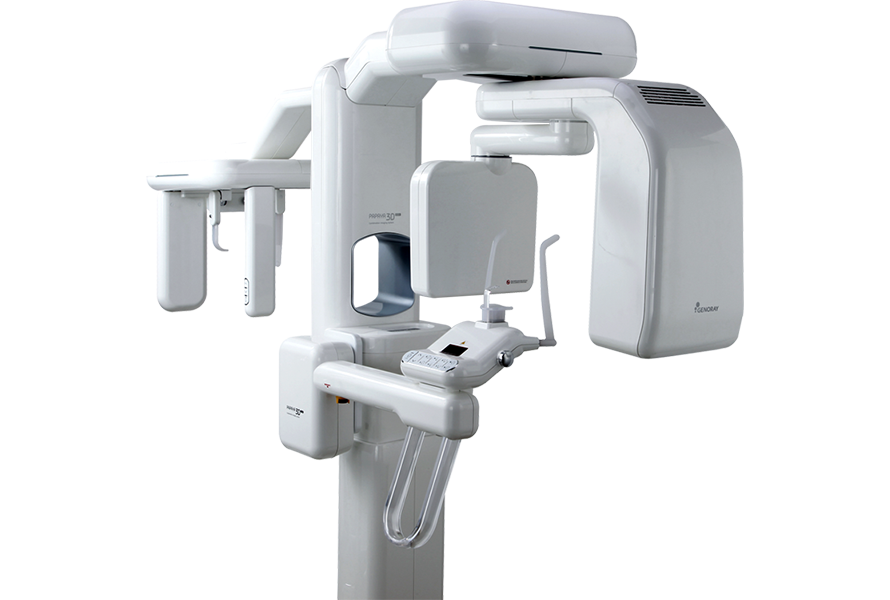

РЕНТГЕНОВСКАЯ СИСТЕМА 4в1

Путем преобразования полученных изображений КТ в STL формат вы можете подготовить цифровую модель для дальнейшей интеграции и получения конструкции в CAD/CAM системах.